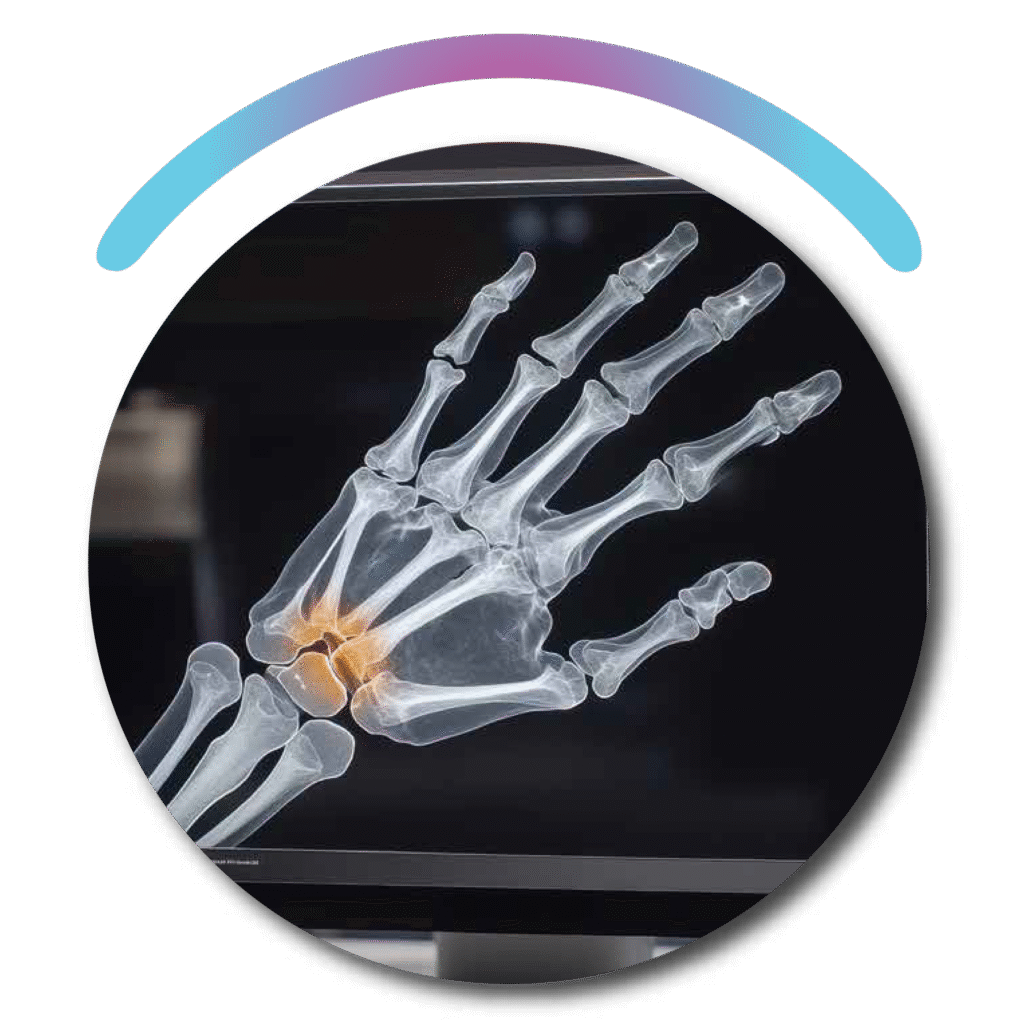

BONE FRACTURE DETECTION

Designed to support emergency and orthopedic care, our AI solution quickly detects bone fractures in X-rays and CT scans with high precision. It helps medical teams identify even subtle or overlooked fractures, ensuring timely and accurate diagnosis. This improves patient safety, reduces diagnostic errors, and speeds up treatment decisions.